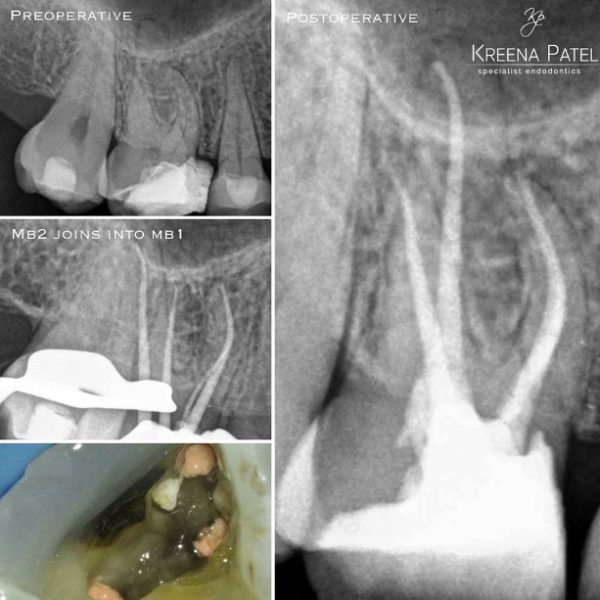

I strongly advise fully preparing the MB1 canal prior to locating and instrumenting MB2. The MB2 often joins MB1 at a sharp angle. It makes negotiation much easier if the MB1 is already enlarged (Figure 10).

Figure 10: Two cases showing MB2 joining MB1 in the mid-third of the root

- Master cone shows MB2 joining MB1

- MB2 joins MB1 at an acute curvature (white arrow).